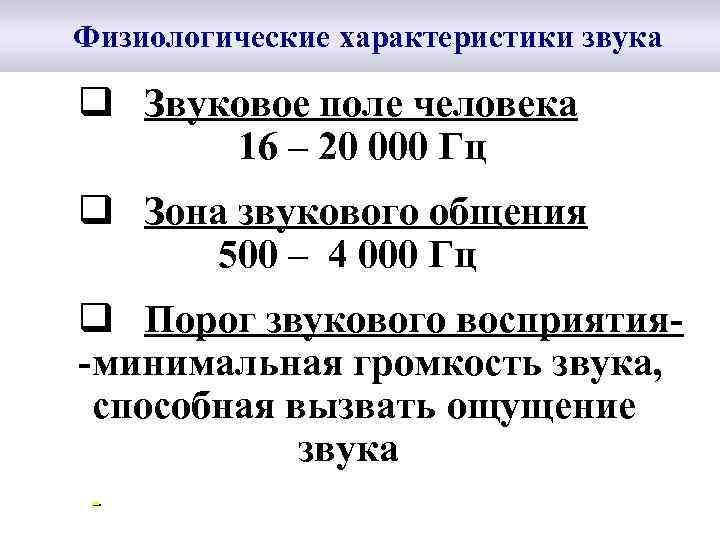

Физиологические характеристики звука q Звуковое поле человека 16 – 20 000 Гц q Зона звукового общения 500 – 4 000 Гц q Порог звукового восприятия-минимальная громкость звука, способная вызвать ощущение звука